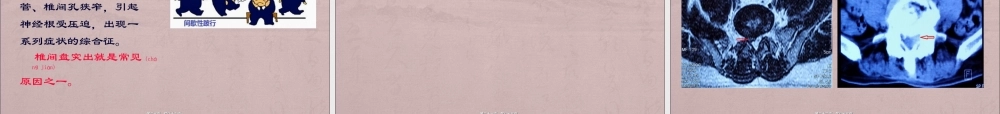

腰腿痛知识讲座关节病科疼痛(téngtòng)科杨洸第一页,共八十九页。第一页,共八十九页。腰腿痛的概念腰腿痛的概念(GÀINIÀN)(GÀINIÀN)以腰部和腿部疼痛为主要(zhǔyào)症状的伤科病症,主要(zhǔyào)是由椎间盘突出、腰肌劳损等诱发。以25-50岁长期体力劳动或长期久坐人群为多发。本病病程缓慢,所以人们往往不太重视,绝大多数的人不到严重影响工作生活时不会就医,以致延误病情,导致治疗效果不佳,甚至难以治愈,造成终生痛苦。第二页,共八十九页。第二页,共八十九页。腰痛轻者,经休息可缓解,再遇外伤或受风寒湿、劳累仍可复发;腰痛重者,疼痛可向大腿后侧、小腿后外侧及脚外侧放射,转动、咳嗽、喷嚏时加剧(jiājù)。有的患侧小腿外侧或足背有麻木感,甚至可出现间歇性跋行。甚至肌肉萎缩。第三页,共八十九页。第三页,共八十九页。腰腿痛是常见病,80%的成年人都有过腰腿痛。中国缺乏统计数字,根据美国国家统计局的数字显示,美国全国有400万工人因腰痛不能工作。腰腿痛只是(zhǐshì)一个症状,引起腰腿痛的原因很多。其中腰椎间盘突出症最为多见。第四页,共八十九页。第四页,共八十九页。腰椎间盘结构腰椎间盘结构(JIÉGÒU)(JIÉGÒU)腰椎(yāozhuī)从上向下,担负身体80%的重量。椎间盘越厚,越具有较强的弹性缓冲能力,同时也说明弹性协调空间大,灵活度高。在退变损伤过程中,腰椎首当其冲。腰4腰5阶段多突出。第五页,共八十九页。第五页,共八十九页。重要重要(ZHNGYO)ÒÀ(ZHNGYO)ÒÀ的的生理曲度生理曲度健康人腰椎向前凸,椎体之间前宽后窄,髓核中间的受力方向向前。一旦(yīdàn)长时间久坐,腰椎生理曲度消失或变浅时,髓核受力方向朝后,就容易出现腰椎间盘突出。所以对于经常久坐的人群,定时站起来活动活动腰部,保持良好的生理曲度,是很好的预防腰椎疾病的方法。一定要保护好我们的腰椎生理曲度!第六页,共八十九页。第六页,共八十九页。腰椎间盘突出常见于体力工作者、司机、文秘、教师、长期伏案工作的人群,以及长时间有不良姿势(zīshì)者。发病率高,发病人群广,成为急需解决的问题。第七页,共八十九页。第七页,共八十九页。发病(fābìng)人群广、各年龄阶段腰椎间盘突出症发病人群由原来的中年人年龄段扩展(kuòzhǎn)至青少中壮,范围大,涵盖人群广。我治疗年龄最小的腰突症病人是13岁,巨大型突出,保守治疗无效而最终手术治疗。第八页,共八十九页。第八页,共八十九页。椎间盘椎间盘...